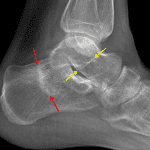

Red arrows: calcaneal stress fracture. Yellow arrows: possible additional stress fracture involving the talar neck.

• Linear band of sclerosis in the calcaneus

• Linear sclerotic band extending through the talar neck with possible minimal cortical offset along the inferior margin, only seen on the lateral view

• Calcaneal stress fracture

• Possible talar neck stress fracture

Linear band of sclerosis in the calcaneus concerning for calcaneal stress fracture.

Linear sclerotic band extending through the talar neck with possible minimal cortical offset along the inferior margin (only seen on the lateral view), concerning for a talar neck stress fracture.